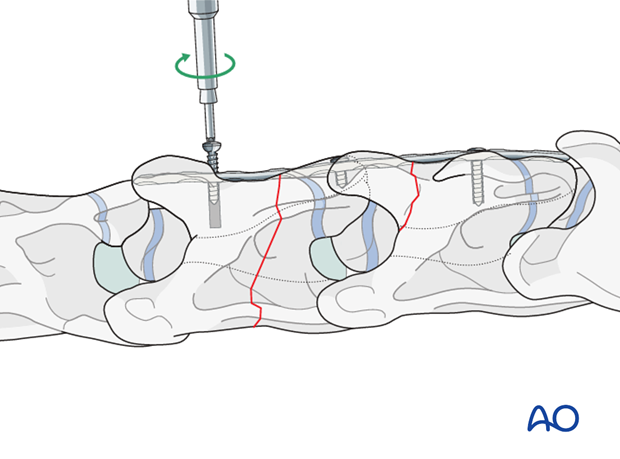

Cortex screws are used in lag fashion on both sides of the fracture to compress the fragments. The length of the screws is determined with the help of fluoroscopy.

Note: Attention must be paid not to damage the spinal cord.

Note: It is difficult to get a secure screw purchase in vertebral bone, particularly in foals, due to the thin cortex of the vertebrae.

The remaining holes are filled with locking-head screws.